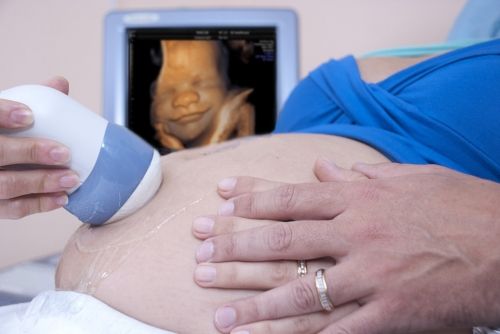

Une femme se sait mère quand, à sa première échographie, elle ne peut retenir ses larmes d’émotion en écoutant le cœur de son enfant battre rapidement, tout comme le sien quand elle déborde de joie à ce premier contact.

Cependant, cette maman sait que pour le moment et pour au moins neuf mois, elle devra se contenter des images que les rayons X montrent afin de mettre un visage sur son fils, en ressentant ces mouvements subtils du bébé, qui deviendront plus actifs.